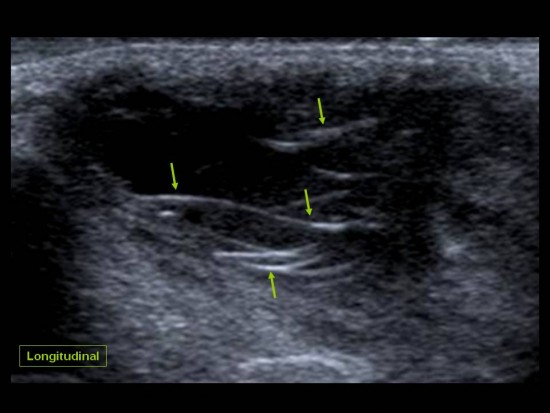

Patient de 44 ans presentant une masse peu sensible de la face palmaire du poignet avec des.

Une anomalie des membres caracterisee par labsence congenitale dun membre a partir du coude. Tumeurs pseudo tumeurs thrombose veineuse ulnaire du poignet irm.